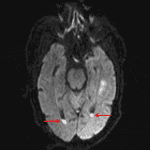

- Area of T2/FLAIR signal hyperintensity centered in the left inferior temporal gyrus with mild gyral expansion and associated central restricted diffusion and faint peripheral enhancement. Faint T2 hypointense rim about the area of restricted diffusion in the left temporal lobe

- Additional areas of FLAIR signal hyperintensity and restricted diffusion within left parietooccipital sulci as well as layering in the occipital horns of the bilateral lateral ventricles with mild diffuse dural thickening and enhancement

Findings concerning for late cerebritis/early abscess in the left inferior temporal gyrus with evidence of meningitis and ventriculitis. These findings likely represent a complication of left ostomastoiditis given proximity, which could be further evaluated with contrast-enhanced temporal bone CT. Recommend ENT and neurosurgical consultation.